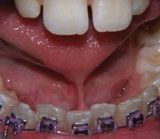

- Frenulectomia

Applicazioni Cliniche